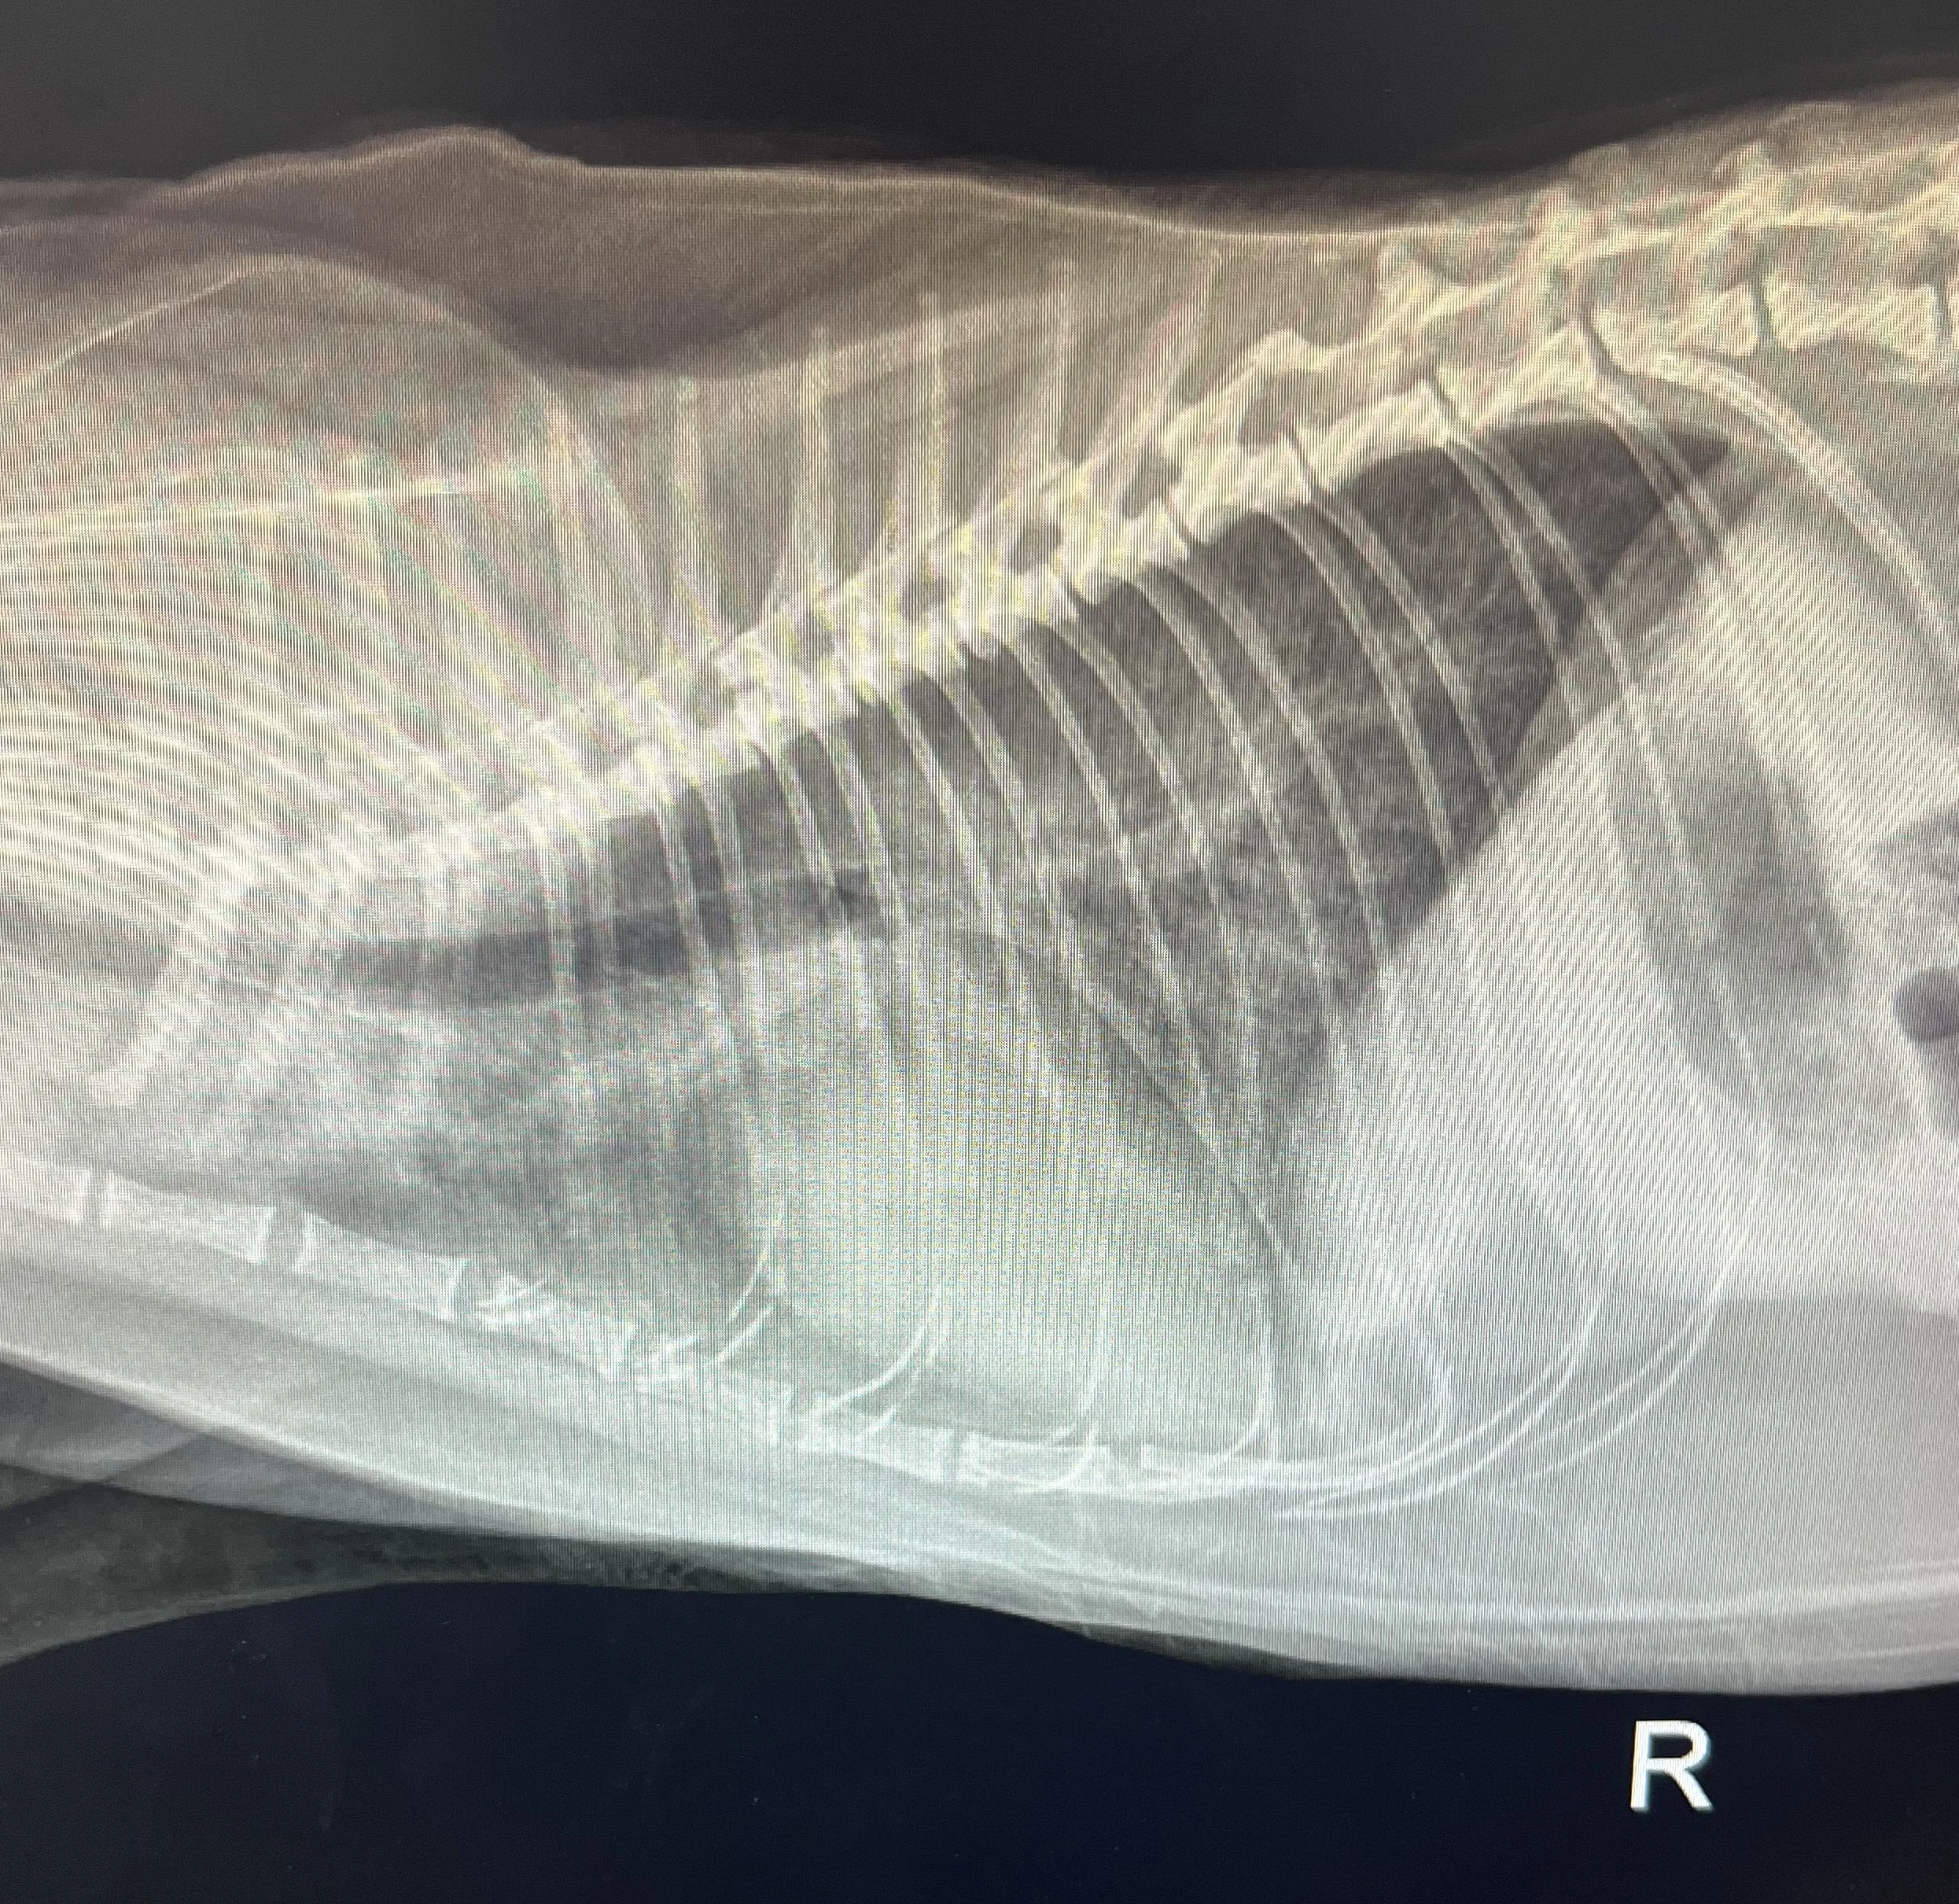

Additional Testing

Results of the diagnostics at a routine visit may warrant further testing (i.e. radiographs, bloodwork, or blood pressure). If these tests are recommended, we can help guide you in the right direction to make sure your pet is well taken care of during the process.